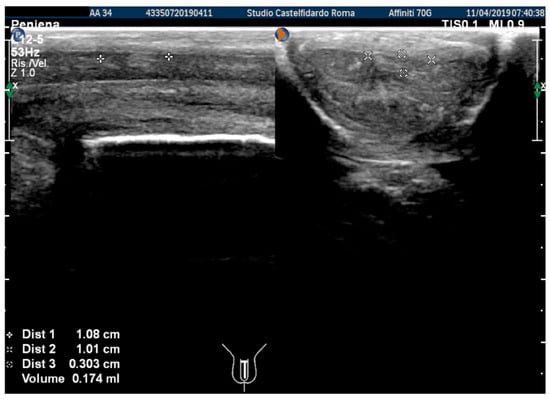

The plaque was located in the middle of the penis, its ultrasound aspect was iso-hyperechoic, and it measured 10.8 × 10.1 × 3.03 mm (174 mm3 = volume) (Figure 1, Table 1).

Figure 1. Ultrasonography of the penis before therapy (longitudinal and axial views).